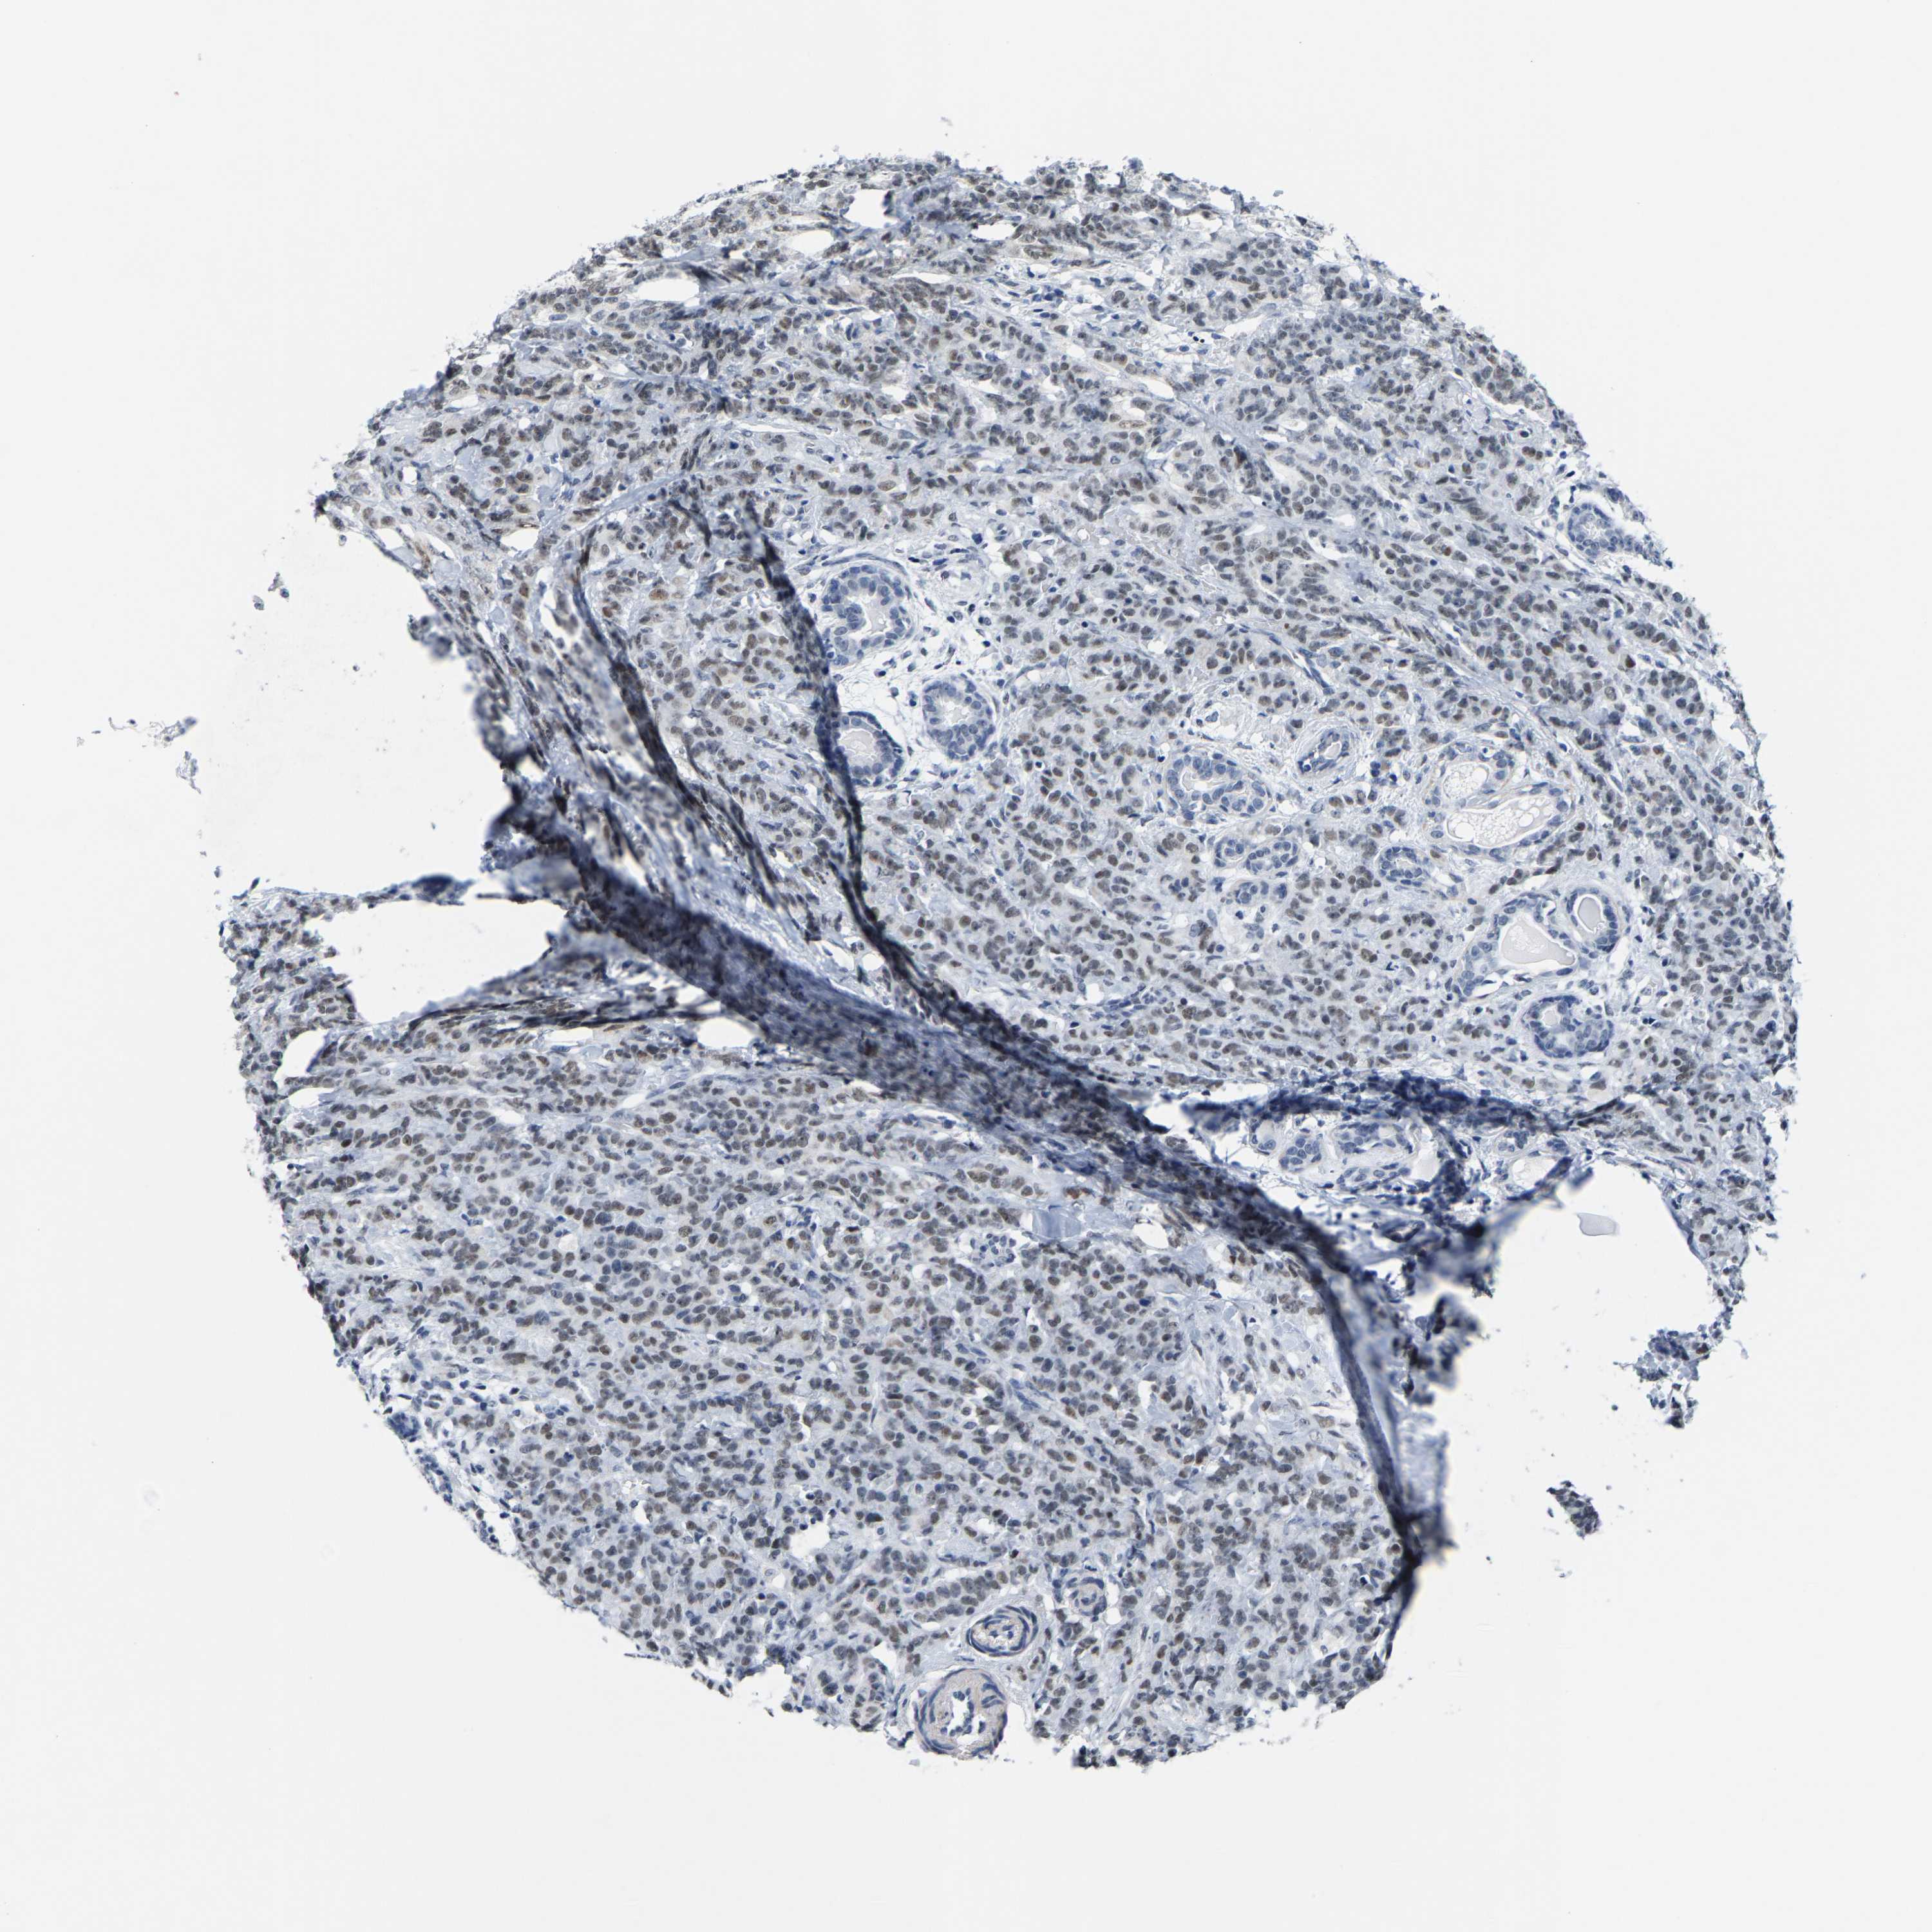

CANCER BREAST CANCER Show tissue menu

BRCA TCGA BRCA VALIDATION PROTEIN EXPRESSION